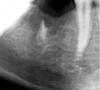

Doc Опубликовано 10 января, 2007 Поделиться Опубликовано 10 января, 2007 Вообщето , имплант противопоказано имплантировать на место доброкачественных опухолей. Это само собой, но как-то слабо аргументировано наличие там цементомы. На снимке вообще трудно определить есть там что-то или нет. Они ее как диагностировали? Просто "нашли" или гистологию брали или как-то еще? Ссылка на комментарий

X-RDV Опубликовано 15 мая, 2007 Поделиться Опубликовано 15 мая, 2007 РЕНТГЕНОЛОГИЧЕСКИ - ЦЕМЕНТОМЫ НЕТ. еСЛИ НЕ ДЕЛАЛАСЬ ГИСТОЛОГИЯ - ЭТО ВЫМЫСЕЛ ЛЕЧ ВРА. Ссылка на комментарий

X-RDV Опубликовано 16 мая, 2007 Поделиться Опубликовано 16 мая, 2007 Вот классическая цементома. Вполне возможно. Надо бы орто посмотреть. Я тут немножко с фотографией поработал – гиперцементоза там тоже нет. Однако, плотность костной ткани вокруг огрызка снижена на 30%.А вот на счет того что : цитата: сходную рентгенологическую картину дают и одонтома, и остеобластома, и фокальный склерозирующий остеомиелит, и гиперцементоз.- тут вы, доктор явно погорячились или не подумали. Ссылка на комментарий